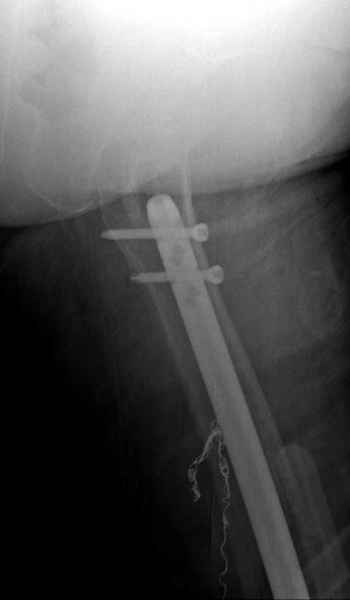

С минимальным рассверливанием и ретроградным методом провели остеосинтез бедра 12 мм гвоздем. (17-20)

Кровопотеря во время операции меньше 100 мл.

Больная выписана, взятый во время рассверливания материал изучается.